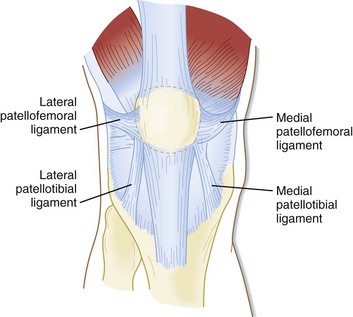

Where or Where Has My Patella Gone Direct Orthopedic Care 2024, Patella Kneecap Anatomy and Function 2024, Patellofemoral Pain Syndrome OrthoInfo AAOS 2024, The Patella Surface Anatomy Functions Dislocation 2024, Patella Wikipedia 2024, Patellar Fractures Broken Kneecap OrthoInfo AAOS 2024, Patellofemoral Joint Structure Function Conditions 2024, Patellofemoral Joint Physiopedia 2024, Patellar region Flashcards Quizlet 2024, Patella Injury Treatments Knee Surgeons Consultants Yorkshire 2024, Patella Anatomy function and clinical aspects Kenhub 2024, Patellar Tendonitis Jumper s Knee Johns Hopkins Medicine 2024, ITB vs Patellofemoral Pain Syndrome Symptoms Knee Pain In Runners 2024, Patellofemoral Pain Syndrome OrthoInfo AAOS 2024, Patella Anatomy function and clinical aspects Kenhub 2024, Patellar Tendonitis Jumpers Knee Symptoms Diagnosis Treatment 2024, Patellofemoral Pain Syndrome Rural Physio at Your Doorstep 2024, Patellar tendinitis Symptoms causes Mayo Clinic 2024, Patella Femoral Syndrome Montgomery Massage Therapy 2024, Jumper s Knee Symptoms in Kids Jumper s Knee Treatment 2024, Anatomy of Patella Bone and Spine 2024, Patellar Tendonitis Jumper s Knee Symptoms Causes Mount 2024, Anatomy Gruppo Bioimpianti 2024, Patellofemoral Pain Syndrome 2024, Patella Tendinopathy also known as Jumper s Knee Complete Physio 2024, Patellofemoral Pain Syndrome PFPS Symptoms Treatment 2024, Patellar Tendonitis 2024, Patellofemoral Joint Physiopedia 2024, How to avoid Runner s Knee . Forty two percent of all overuse 2024, Osgood Schlatter Disease Knee Pain OrthoInfo AAOS 2024, Tendinitis in the Knee 2024, Patella Kneecap Definition Location Anatomy Diagram 2024, Patellar Tendinopathy Rural Physio at Your Doorstep Physio Direct 2024, Knee Pain Location Chart SPORT Orthopedics Dallas and Frisco 2024, 10 Common Knee Injuries Diseases 2024.

Where or Where Has My Patella Gone Direct Orthopedic Care 2024, Patella Kneecap Anatomy and Function 2024, Patellofemoral Pain Syndrome OrthoInfo AAOS 2024, The Patella Surface Anatomy Functions Dislocation 2024, Patella Wikipedia 2024, Patellar Fractures Broken Kneecap OrthoInfo AAOS 2024, Patellofemoral Joint Structure Function Conditions 2024, Patellofemoral Joint Physiopedia 2024, Patellar region Flashcards Quizlet 2024, Patella Injury Treatments Knee Surgeons Consultants Yorkshire 2024, Patella Anatomy function and clinical aspects Kenhub 2024, Patellar Tendonitis Jumper s Knee Johns Hopkins Medicine 2024, ITB vs Patellofemoral Pain Syndrome Symptoms Knee Pain In Runners 2024, Patellofemoral Pain Syndrome OrthoInfo AAOS 2024, Patella Anatomy function and clinical aspects Kenhub 2024, Patellar Tendonitis Jumpers Knee Symptoms Diagnosis Treatment 2024, Patellofemoral Pain Syndrome Rural Physio at Your Doorstep 2024, Patellar tendinitis Symptoms causes Mayo Clinic 2024, Patella Femoral Syndrome Montgomery Massage Therapy 2024, Jumper s Knee Symptoms in Kids Jumper s Knee Treatment 2024, Anatomy of Patella Bone and Spine 2024, Patellar Tendonitis Jumper s Knee Symptoms Causes Mount 2024, Anatomy Gruppo Bioimpianti 2024, Patellofemoral Pain Syndrome 2024, Patella Tendinopathy also known as Jumper s Knee Complete Physio 2024, Patellofemoral Pain Syndrome PFPS Symptoms Treatment 2024, Patellar Tendonitis 2024, Patellofemoral Joint Physiopedia 2024, How to avoid Runner s Knee . Forty two percent of all overuse 2024, Osgood Schlatter Disease Knee Pain OrthoInfo AAOS 2024, Tendinitis in the Knee 2024, Patella Kneecap Definition Location Anatomy Diagram 2024, Patellar Tendinopathy Rural Physio at Your Doorstep Physio Direct 2024, Knee Pain Location Chart SPORT Orthopedics Dallas and Frisco 2024, 10 Common Knee Injuries Diseases 2024.